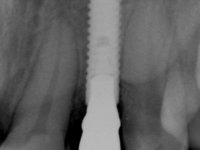

Female patient, 24 years of age, non-smoker. The clinical situation resulted from an orthodontic treatment performed with the intention of resolving a problem of unilateral agenesis of the left lateral incisor. After orthodontic correction, an implant was placed at the site of tooth 2.2. During the period of osseointegration the patient used a removable orthodontic appliance with a prosthetic tooth. Upon assessment of the situation, I registered the following aesthetic conditions:

An impression was made on the implant with open tray technique using soft and regular consistency putty. At the laboratory, after confection of the work model, a diagnostic waxing was performed, which sought to find an aesthetic compromise solution. In this sense, a temporary workpiece screwed onto the implant was used to simulate the difficulties we would have with screwing the definitive work. This study abutment consisted of wax to reproduce soft and hard tissues, seeking to anticipate the use of ceramics of gingival and coronary shade. Also, part of the interproximal papillae corresponding to the distal portion of the 2.1 tooth and the mesial tooth of the tooth 2.3 were also waxed, anticipating the use of composite resin “chips” with gingival tonality. Finally, a veneer was waxed to correct the microdontia of the tooth 1.2. In this waxing, the vestibular emergence of the orifice for access to the screw of the implant abutment was evident. Once this therapeutic option was accepted, the implant abutment in polymerized composite resin was prepared at the lab, as well as the papillary "chips", also in composite resin of gingival tonality. Tested in the mouth, the abutment was screwed and the "chips" bonded. The access hole of the screw was filled with composite resin. In subsequent consultation, a gingivectomy was performed on the cervical contour of teeth 1.3, 1.2 and 1.1 with the aim of correcting the asymmetry between the first and second quadrant. After the soft tissues were cicatrized, a dental bleaching was performed according to the patient’s aesthetic requirements. Final impression on the implant was made using the silicone open tray technique, taking care to individualize the transfer piece by copying the emergence profile of the patient’s provisional abutment. At the laboratory, the impression yielded a definitive working model, on which the abutment was waxed on a plastic insert. This process was carried out with the orientation of a wall of silicone based on diagnostic waxing. The wax made on the plastic part was placed in a special holder that allowed its scanning in a laboratory scanner. This scan by CAD process informed the design of an abutment in Zr. later materialized by a CAM process. The Zr. abutment was tested in the mouth, validating its clinical and imaging establishment. During this consultation, the choice of color was made by the ceramist, of both the coronary ceramics and the ceramic of gingival tonality to be used. Individualized color scales were used. At the laboratory, the coronary and gingival ceramics were placed on the implant abutment and later, on a working model with refractory gypsum, a veneer of feldspathic ceramic was made. This veneer was built on a surface specially designed for this purpose in the abutment. This surface tried to reproduce a dental preparation performed for the same effect. In the mouth the abutment was screwed with a torque of 35N, the access hole to the screw was filled with Teflon and later filled with composite resin. The veneer was bonded onto the implant abutment using the conventional bonding technique, with relative insulation. For economic reasons, the patient did not proceed to perform the veneer on tooth 1.2. Although a limited aesthetic compromise was expected from the outset, a result was achieved which satisfied the patient.